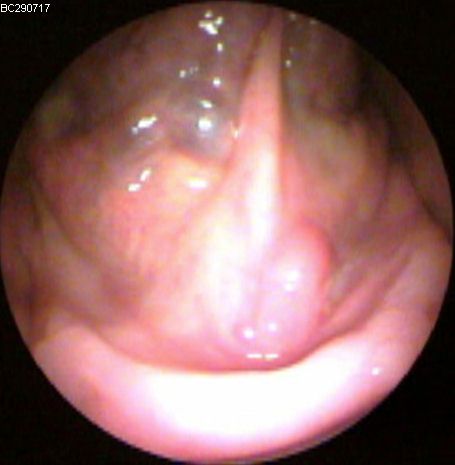

JFC Aticotomía espontánea.